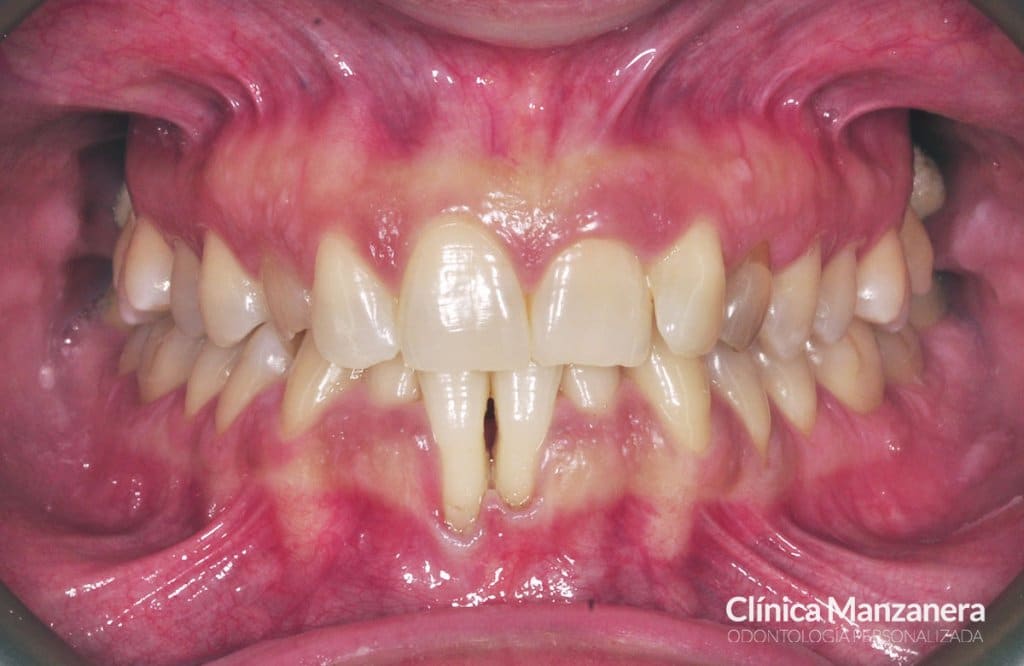

Inicialmente, presentaba una situación con varios elementos que complicaban el tratamiento como podéis ver en las fotos: presencia de un canino incluido (colmillo derecho), ausencia del canino izquierdo, apiñamiento inferior severo, compresión de la arcada superior e inferior (paladar estrecho), y grandes recesiones gingivales (pérdida altura de la encía) en los incisivos centrales inferiores.

Sonrisa antes